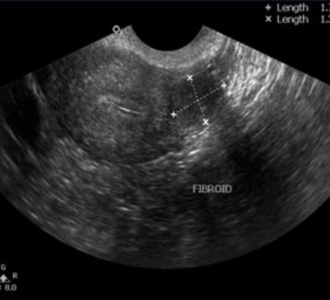

Uterine causes

Abnormal uterine shapes (Septate uterus, bicornuate uterus), Fibroid uterus,